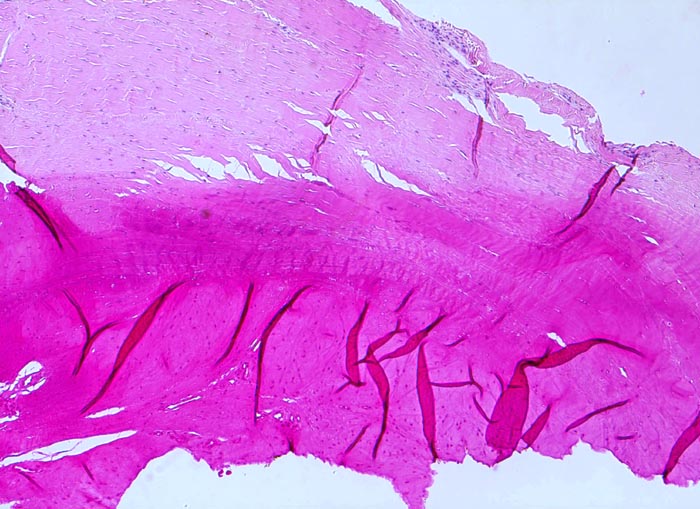

Synovialitis bei chronischer Polyarthritis

Straffes kollagenes Bindegewebe möglicherweise entsprechend einer Sehne. Das fokal ausgetrocknete Gewebe ist dunkelrot verfärbt und weist zahlreiche Falten auf, die beim Aufziehen des Schnittes auf den Objektträger entstanden sind. Die Einrisse sind ebenfalls artefiziell bei der Gewebsentnahme bzw. Gewebsverarbeitung entstanden.

Eine artefizielle unregelmässige Einfärbung des Schnittes kann aus einer fokalen Austrocknung des Gewebes, einer inhomogenen Schnittdicke oder einer ungleichmässigen Inkubation in der Farblösung resultieren.